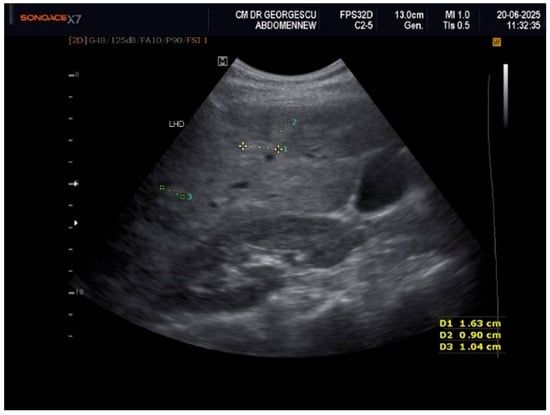

Liver Lipodystrophy in Barraquer–Simons Syndrome: How Much Should We Worry About?

Lipodystrophy is a rare group of metabolic disorders characterized by the abnormal distribution of body fat, which can lead to various metabolic complications due to the body’s inability to adequately process carbohydrates and fat. We report the case of a female, aged 53 years, who was admitted as an outpatient for progressive weight loss of the upper part of the body (face, neck, arms, and chest), dyspeptic complaints, fatigue, mild insomnia, and anxious behavior. Her medical history was characterized by the presence of dyslipidemia, hypertension, and a minor stroke episode. However, she denied any family-relevant medical history. Although the clinical perspective suggested a possible late onset of partial acquired lipodystrophy, due to the imaging exam that revealed an enlarged liver with inhomogeneous structure with multiple nodular lesions, scattered over both lobes, a lot of lab work-ups and complementary studies were performed. Eventually, a liver biopsy was performed by a laparoscopic approach during cholecystectomy, the histology consistent with metabolic disease-associated steatohepatitis (MASH). In conclusion, given their heterogeneity and rarity, lipodystrophies may be either overlooked or misdiagnosed for other entities. Barraquer–Simons syndrome (BSS) may be associated with liver disease, including cirrhosis and liver failure. Liver lipodystrophy in BSS may sometimes feature steatosis with a focal, multi-nodular aspect, multiplying the diagnostic burden. Liver lipodystrophy may manifest as asymptomatic fat accumulation but may progress to severe conditions, representing one of the major causes of mortality in BSS, apart from the cardio-vascular comorbidities. Given the potential of severe outcomes, it is mandatory to correctly assess the stage of liver disease since the first diagnosis. Full article

Figure 1